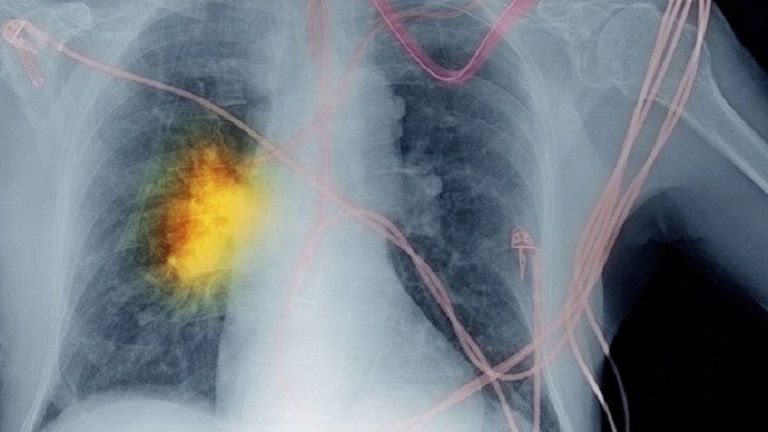

سرطان الرئة.. عقار جديد يبشر بالخير

مقاومة الأدوية التي تعالج الشكل الأكثر شيوعاً لسرطان الرئة أمر شائع، لكن الخبر السار أن باحثين توصلوا لعقار جديد نتائجه تبشر بالخير.

سرطان الرئة هو ثاني أكثر السرطانات التي يتم تشخيصها بشكل شائع في جميع أنحاء العالم والسبب الرئيسي لوفيات السرطان.